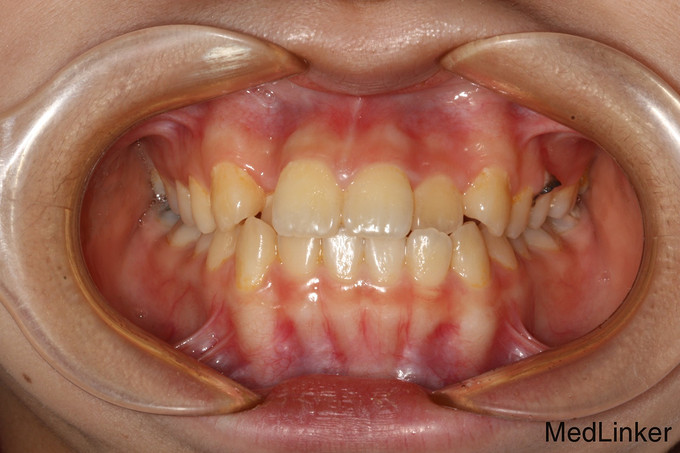

儿童牙齿矫正

14岁儿童,因牙齿生长缺陷牙列不齐,影响美观需矫正。